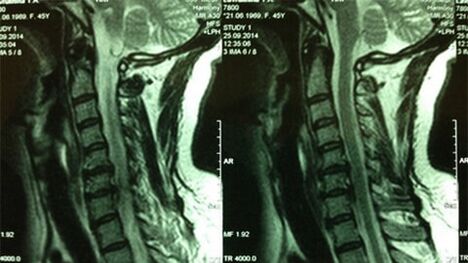

- X -ray of the cervical department;At the initial stage of the process, the MRI of the cervical department will be more informative - it will ensure high -quality visualization of solid and soft tissues - will show the condition of the intervertebral discs, the presence of osteophytes, deformations, damage to the nerve roots and blood vessels;will evaluate the condition of the ligaments, muscles, bone tissue;